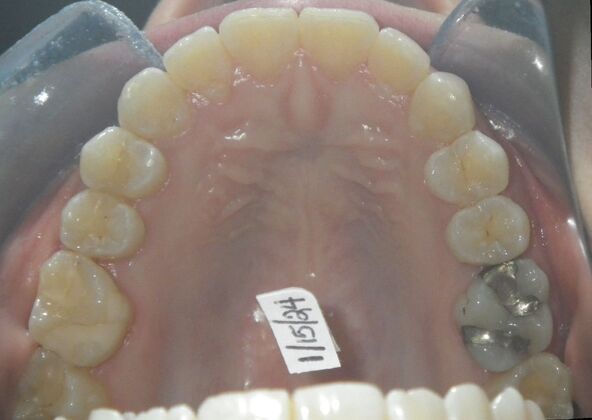

This patient had concerns with the lower anterior teeth. There were some slight rotations and the midline of the lower incisors wasn't lined up with the upper midline. To correct this we used slenderizing of teeth in strategic areas of the lower arch to correct the rotations and line up the midlines. Patient very pleased with the results.